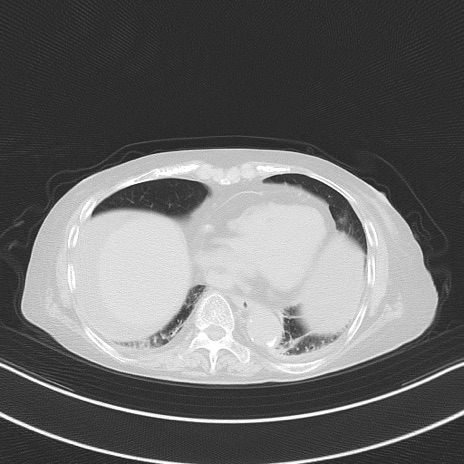

横断像

他院CT